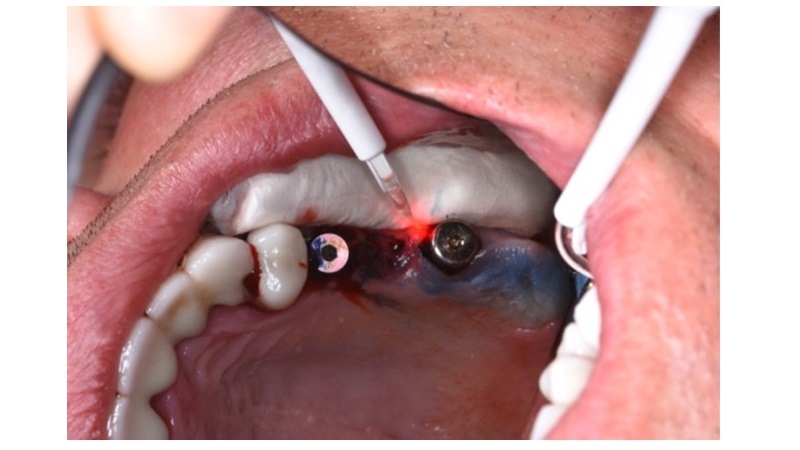

- ایمپلنت دندان اصفهان

- جراحی دندان در اصفهان

درد دندانهای مجاور پس از کاشت ایمپلنت یکی از مشکلاتی است که برخی بیماران تجربه میکنند. این در...